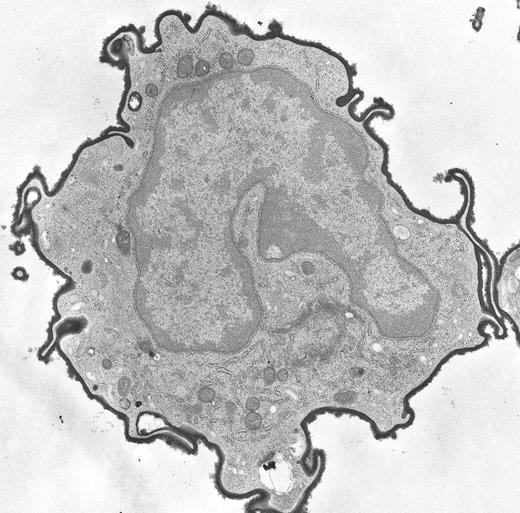

Esterase ectoenzyme on the cell surface of a peripheral blood monocyte from a patient with mycosis fungoides. (Original magnification × 14,500.) (Courtesy of Ann M. Dvorak, MD, Department of Pathology, Beth Israel Hospital, Harvard Medical School, 330 Brookline Ave, Boston, MA 02215.)